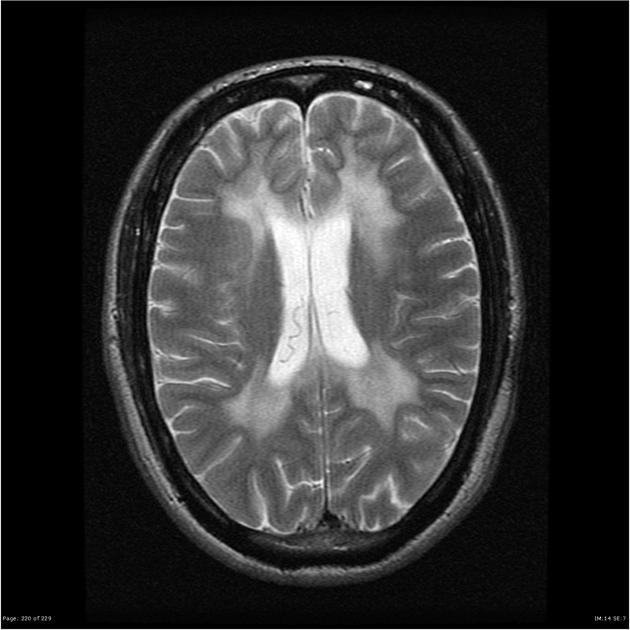

La malattia consiste in un accumulo di una sostanza metacromatica (determina viraggio del colore della luce trasmessa) birifrangente, costituita da accumuli di sulfatidi nella sostanza bianca (mielina) nelle cellule nervose dell'oligodendroglia, nelle cellule di Schwann e nei nervi in generale. Successivamente le cellule muoiono per fenomeni fibrotici, e le cellule superstiti presentano inclusioni tipiche e non.

La patologia è dovuta ad un deficit geneticamente predeterminato dell'enzima Arilsulfatasi A, con accumulo di sostanza metacromatica nella mielina del SNC e anche nei reni. Varie zone anatomiche del cervello presentano lesioni nella malattia; si hanno anche esiti oftalmologici nel 50 % dei casi per lesioni al nervo ottico con cecità.

Si fa con la dimostrazione del deficit di metabolismo dei sulfatidi, con accumulo degli stessi nelle urine e nei nervi. Inoltre si può anche evidenziare nelle urine il deficit dell'arilsolfatasi di tipo A. Utile, anche, per la diagnosi una biopsia congiuntivale, per evidenziare nelle fibre nervose mieliniche le tipiche inclusioni metacromatiche e l'alterazione strutturale della guaina mielinica.